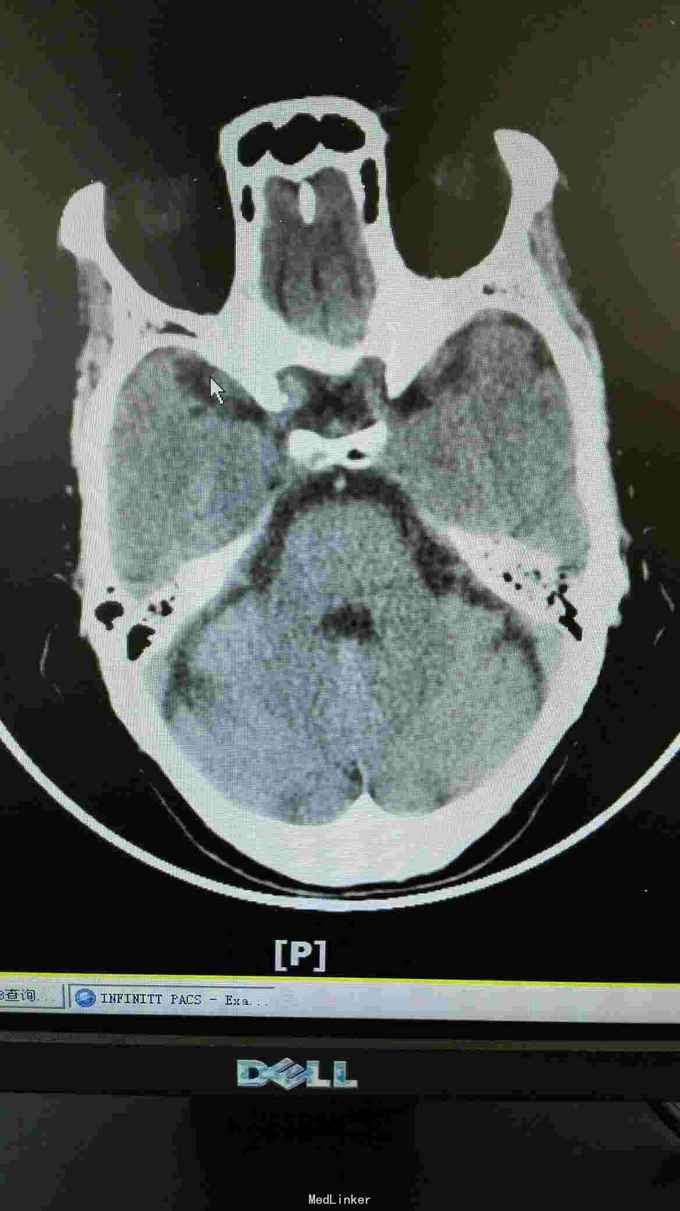

生命体征:耳温:36.8℃ 脉搏:96次/分 呼吸:20次/分 血压:140/67mmHg。pain score: 0/10 发育无异常,口唇无发绀,双肺呼吸音清,未闻及干湿性啰音;心率96次/分,律齐,未闻及明显病理性杂音;腹软,无压痛、反跳痛,肝脾肋下未及,双肾区无叩痛,双下肢无浮肿。神经专科:神清,构音尚清,双侧额纹对称,双眼睑下垂,右侧明显,双侧瞳孔等大等圆,直径约3.0mm,对光++,双眼活动尚可,伸舌居中,鼻唇沟无浅,颈软,四肢肌力5级,双侧肢体肌张力对称,双侧巴氏征未引出,双侧指鼻准,闭目难立征阴性。 血常规三系尚正常。出凝血系列,甲状腺功能 ;存在TSH偏高。肿瘤标志物基本正常范围。糖化血红蛋白正常范围;空腹血糖、血钾正常范围。大小便常规未见明显异常。 胸部CT提示右肺中叶及左肺上叶舌段纤维、增殖灶,请结合临床。颈动脉B超提示左侧颈动脉斑块形成,存在左侧颈动脉硬化。椎动脉B超提示双侧椎动脉未见明显异常。心超提示左室舒张功能下降。腹部B超提示肝、胆、胰、脾未见异常,双肾、输尿管、膀胱未见异常。甲状腺B超提示右侧甲状腺结节。肌电图提示重频试验阴性。心电图提示窦性心律,大致正常心电图。 这个病人因为做过钢板内固定术,所以磁共振没做!可惜了

诊断:双眼睑下垂待查:重症肌无力?动眼神经麻痹待排。2.高血压病?3.心功能不全? 目前治疗上予立普妥20mg调脂稳定斑块,待肌电图检查回报后余新斯的明口服,以及活血化瘀、改善循环等对症支持治疗.

这患者优先考虑重症肌无力,但是以单侧为主,所以动眼神经麻痹也需要排除,因为患者在上级医院做过“新斯的明试验”症状稍改善,持续数小时后又加重,所以等药效过了之后给她做了肌电图,重频试验阴性。1-5波幅下降不明显,结合头颅CT结果,诊断重症肌无力,予新斯的明口服后症状是有改善, 我想请教各位,单单从症状和新斯的明试验可以诊断重症肌无力吗?因为这个病人的肌电图表现是阴性的胸部CT也没看到有胸腺增生。